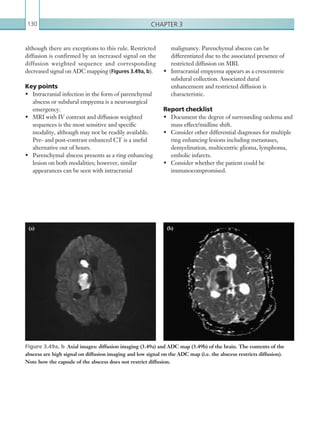

techniques, with a focus on relevant positive and negative findings to pass on to referring

clinicians. On Call Radiology offers invaluable knowledge and practical tips for any

on-call radiologist.

ON CALL

RADIOLOGY

K22247_Cover.indd All Pages 5/21/15 1:52 PM

On call radiology